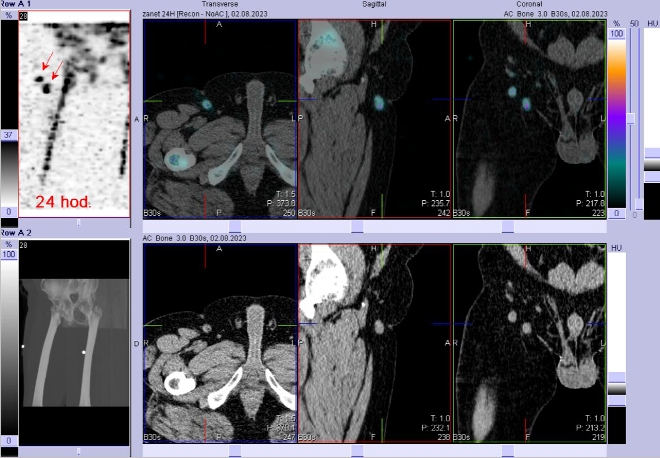

Vyšetření zánětlivého procesu – scintigrafie 08/2023:

Za 3 a 24 hod. po i. v. aplikaci 700 MBq 99mTc - besilesomabu (přípravek

Scintimun firmy Curium Netherlands B.V. = monoklonální protilátky proti granulocytům) jsme provedli celotělové scintigramy a cílenou tomografickou scintigrafii (SPECT) bérců kombinovanou s CT

(obr 4-7) na hybridní tomografické scintilační kameře Symbia T2 firmy Siemens.

/ Obr. č. 5: Fúze obrazů SPECT a CT za 24 hod. po aplikaci radiofarmaka.

/ Obr. č. 6: Fúze obrazů SPECT a CT za 24 hod. po aplikaci radiofarmaka.

/ Obr. č. 7: Fúze obrazů SPECT a CT za 24 hod. po aplikaci radiofarmaka. Radioaktivita v zánětem aktivovaných dvou tříselných uzlinách vpravo.

Popis:

Patologická zánětlivá ložiska - povrchově podkožně v distální části pravého bérce spolu s ložiskem ve stejné lokalizaci na bérci, ale

již postihující kost. Další dvě ložiska v aktivovaných tříselných uzlinách vpravo. Při vyš. 03/2023 bylo patrné pouze povrchové ložisko v distální části pravého bérce v místě kožního defektu, bez postižení kosti.

Závěr

Prokazujeme osteomyelitidu distální části pravé tibie.